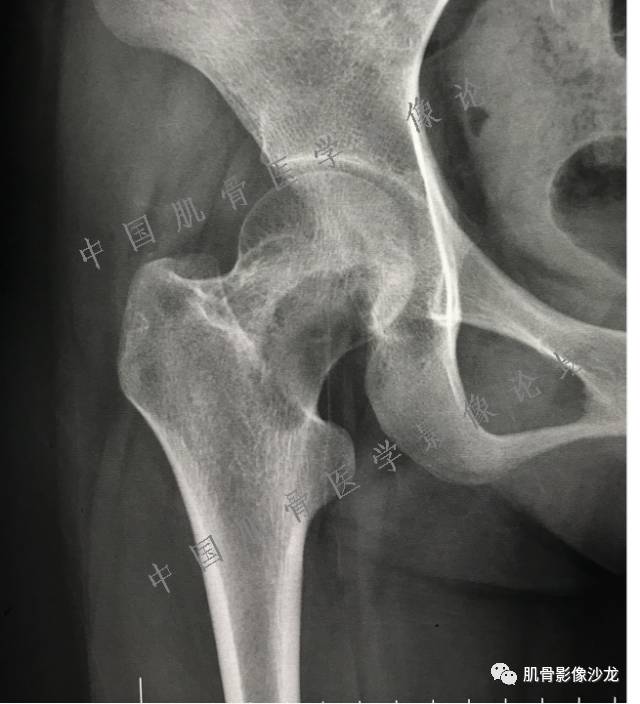

主诉:右大腿疼痛、活动受限20天

现病史:患者于20天前无明显诱因出现右下肢疼痛,活动受限,疼痛呈阵发性,活动后加重。自行口服止痛药芬必得,效果不佳,至当地医院治疗,检查发现右侧股骨近端病变。遂来诊

葛英霖 20:30 原发或继发动脉瘤样骨囊肿,继发于巨细胞瘤,软骨母,纤维组织细胞瘤,骨母等等

向以四 20:30 软骨母合并ABC,

医影在线 20:30 软骨母,/继发ABC

飞鹰行动 20:31 T2信号高,有软骨成分

Echo 20:32 T2确实有一块区域很亮 ,并有野液平

飞鹰行动 20:33 有侵袭性

飞鹰行动 20:35 骨皮质破坏,周围骨质异常信号

葛英霖 20:36 这不是良性病变

葛英霖 20:36 中间型可能性极大

葛英霖 20:37 明显侵蚀骨内膜啊,硬化边也不完整 (细箭头所示)